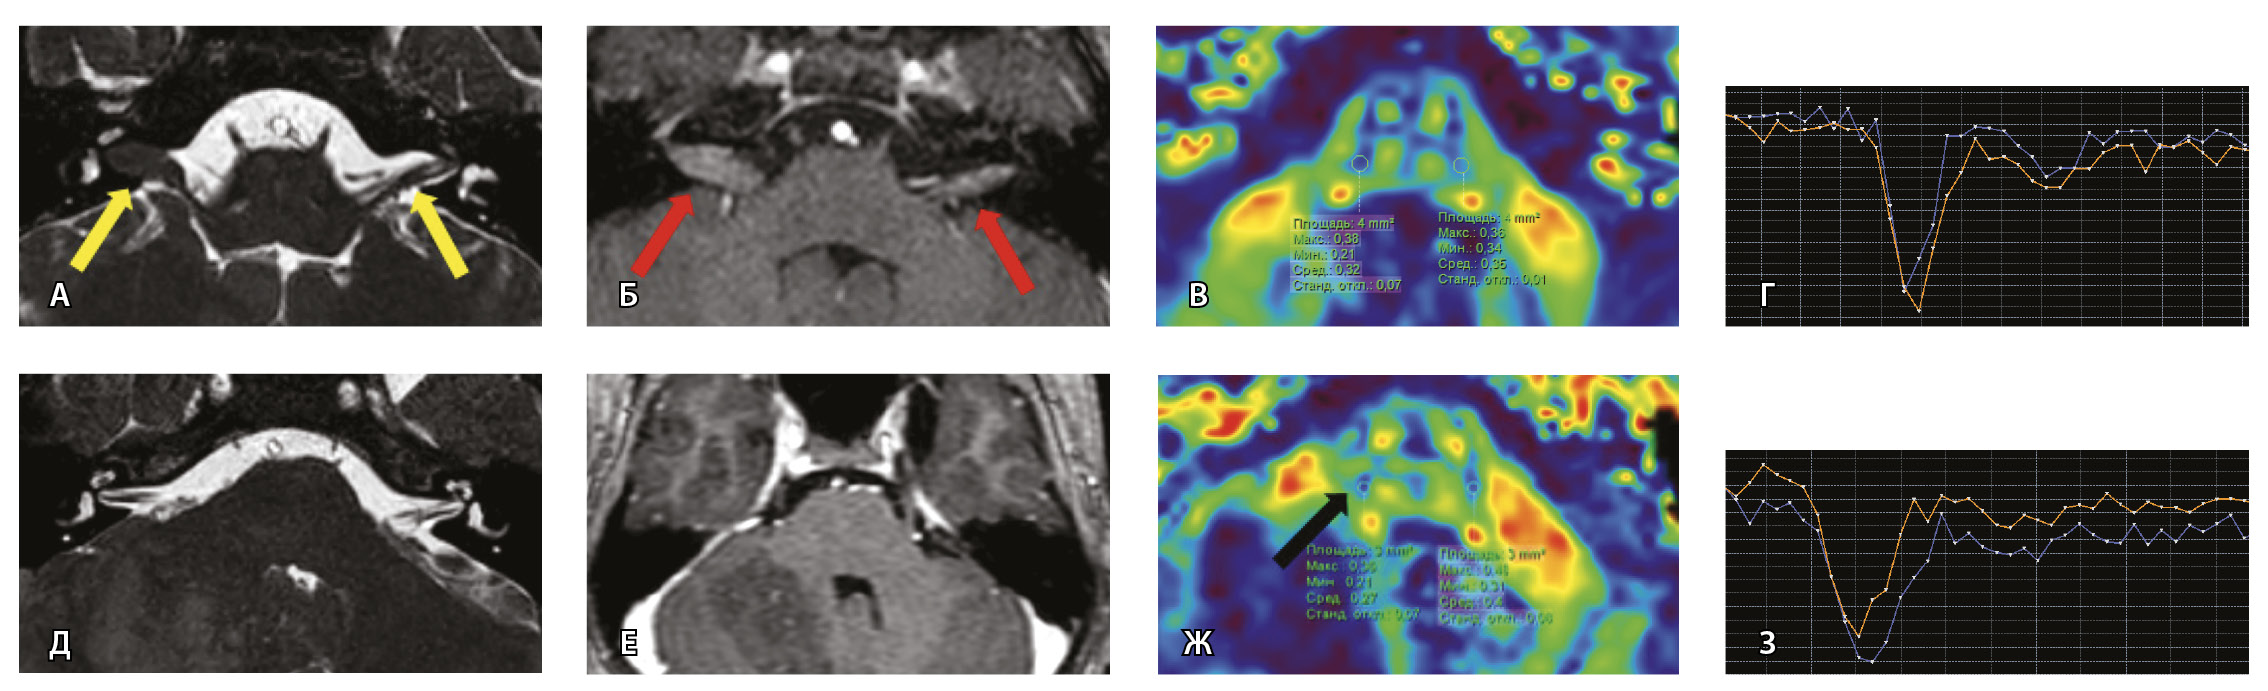

Рис. 7. Клиническое наблюдение 2, пациент 6 лет (А, Б, В, Г). Магнитно-резонансная томография (МРТ) головного мозга: А – прицельная T2-SSFP на область мосто-мозжечкового угла; Б – Т1-взвешенное изображение с контрастным усилением; В – диффузионно-тензорная МРТ (фракционная анизотропия, ФА); Г – Т2*-перфузия. На изображении T2-SSFP отмечается утолщение корешков лицевого, вестибуло-кохлеарного нервов во внутренних слуховых проходах (А, желтые стрелки) и интенсивное накопление ими контрастного вещества (Б, красные стрелки). На уровне моторных ядер лицевых нервов в заднем отделе варолиевого моста значения ФА симметричны (В), признаков гипо-/гиперперфузии не выявлено (Г).

Клиническое наблюдение 3, пациент 13 лет (Д, Е, Ж, З). МРТ головного мозга: Д – прицельная T2-SSFP на область мосто-мозжечкового угла; Е – Т1-взвешенное изображение с контрастным усилением; Ж – диффузионно-тензорная МРТ (ФА); З – Т2*-перфузия. На изображении T2-SSFP патологические изменения на уровне прохождения лицевых нервов во внутренних слуховых проходах не определяются (Д). В медиальном отделе правого полушария мозжечка определяется объемное образование, компримирующее стенку IV желудочка и задний отдел варолиевого моста без признаков васкуляризации (Е). На уровне моторных ядер лицевого нерва в заднем отделе варолиевого моста на изображениях ФА на стороне поражения отмечается минимальное уменьшение показателя ФА до 0,27 (Ж, черная стрелка) и признаки гипоперфузии (З, оранжевый график) по сравнению с контралатеральной стороной (З, синий график)

При этом в клиническом наблюдении № 2 из анамнеза жизни известен ранее установленный диагноз лимфобластного лейкоза в стадии ремиссии. В клиническом наблюдении № 3 значимых анамнестических сведений и данных в пользу атипичного течения ПБ получено не было.

Таким образом, при помощи информации, полученной при проведении МП-МРТ, в обоих случаях был установлен симптоматический характер НЛН, обусловленный развитием неопластических процессов. Оба пациента были направлены в профильные хирургические стационары для проведения дальнейшего лечения.